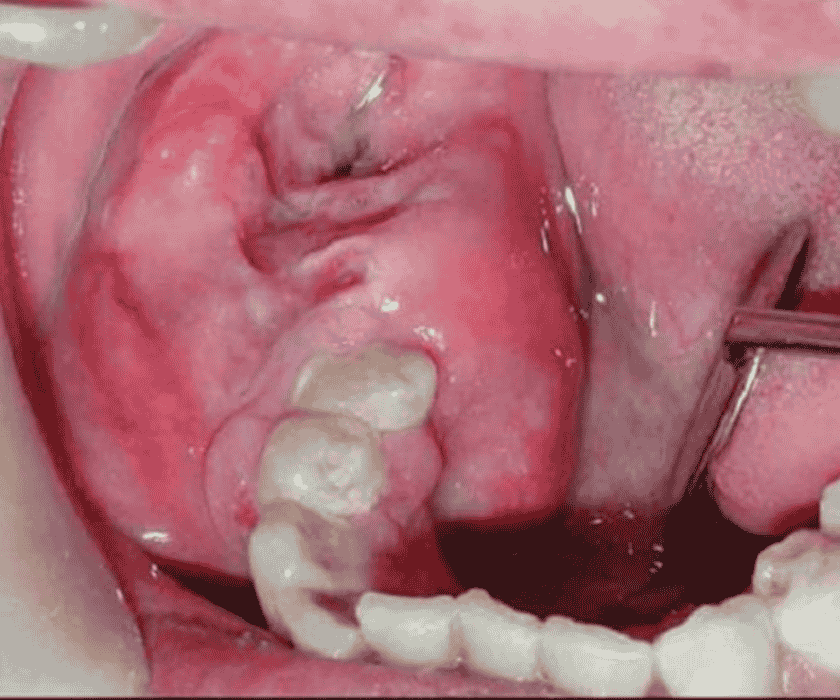

Khi u nang răng khôn được chẩn đoán, bác sĩ sẽ tiến hành phẫu thuật để loại bỏ cả u nang và chiếc răng khôn bị kẹt. Việc này thường đòi hỏi kỹ thuật phức tạp hơn so với nhổ răng khôn thông thường.

- Phẫu thuật loại bỏ u nang và răng khôn

Quy trình phẫu thuật được thực hiện bởi đội ngũ bác sĩ chuyên sâu, giàu kinh nghiệm. Mặc dù là một ca phức tạp, nhưng với sự hỗ trợ của công nghệ Piezotome (sóng siêu âm), bác sĩ có thể thực hiện phẫu thuật một cách nhẹ nhàng, ít xâm lấn, giảm thiểu tổn thương mô mềm và xương. Công nghệ này giúp quá trình nhổ răng khôn diễn ra nhanh chóng, ít chảy máu và giảm sưng đau sau phẫu thuật.

U nang răng khôn do biến chứng mọc kẹt